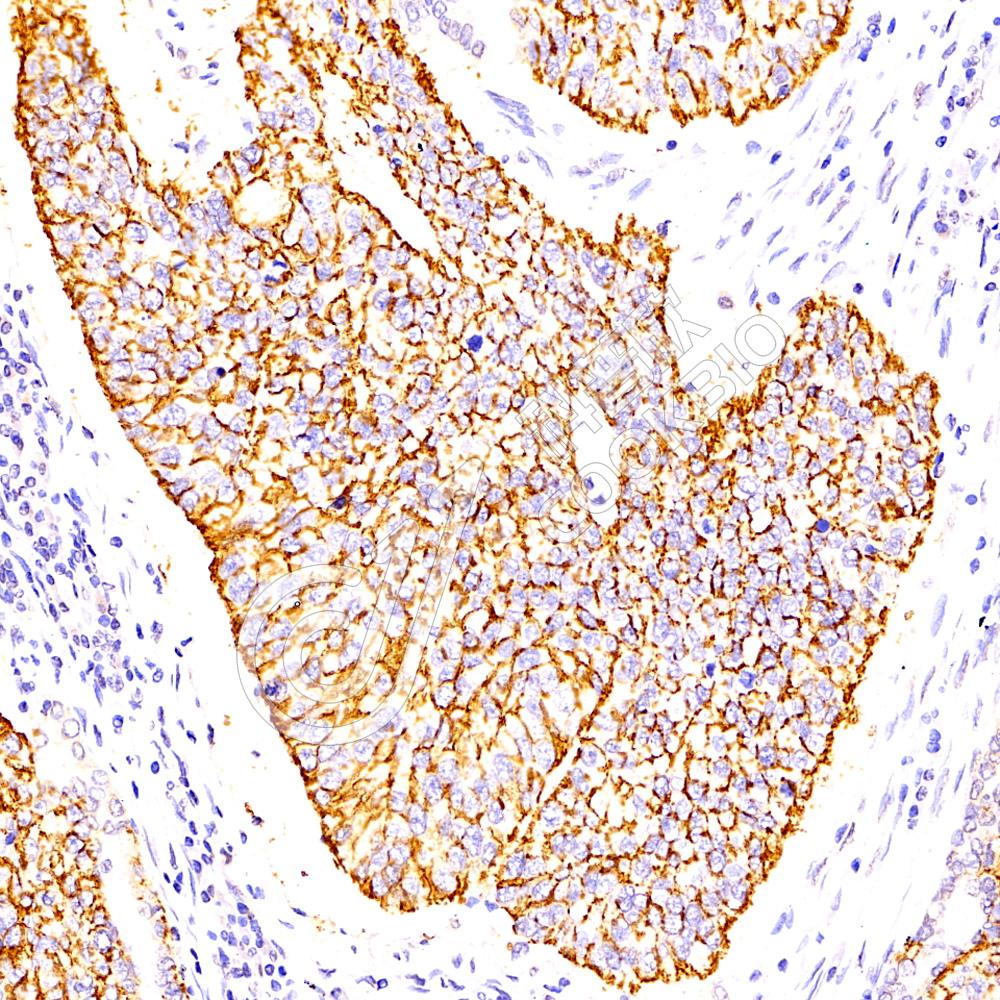

IHC检测Claudin 1蛋白(货号 K1337629).

样品: 人结肠癌, 4%多聚甲醛 (货号KSG1101) 固定12-24小时.

抗原修复: 柠檬酸抗原修复液(干粉, pH 6.0) (KSG1201), 98℃, 20分钟.

—抗: 1: 1400稀释, 4℃ 孵育过夜.

二抗: S-vision免疫组化多聚二抗(山羊抗兔),即用型 (货号KB3906), 室温孵育20分钟.

样品: 人肺癌, 4%多聚甲醛 (货号KSG1101) 固定12-24小时.